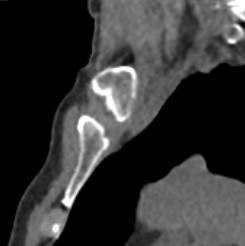

Однако классический рентген не всегда обеспечивает качественную визуализацию ГКС из-за наложения друг на друга изображений костных структур. Компьютерная томография лишена таких недостатков. При проведении КТ излучатель рентгеновских лучей совершает круговые движения вокруг исследуемой области, проводя сканирование в различных плоскостях. В результате получаются детальные снимки высокого качества, а после цифровой обработки – трехмерные модели грудино-ключичных сочленений в мельчайших подробностях.

КТ благодаря быстроте, доступности и высокой информативности часто назначается в экстренных ситуациях, например, при травмах и в случае необходимости проведения оперативного лечения. Поэтому метод особенно востребован в ортопедии и травматологии. На снимках КТ и трехмерных изображениях можно оценить состояние суставных поверхностей грудино-ключичных сочленений, а в случае перелома определить точную локализацию костных отломков.